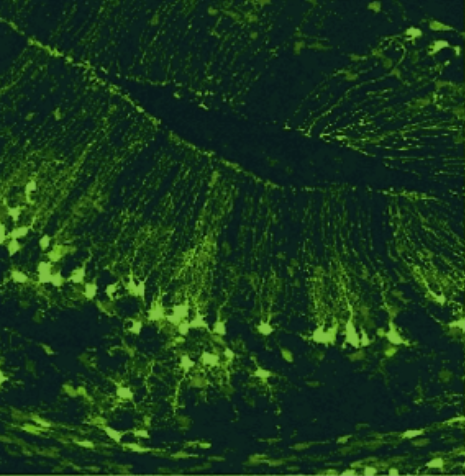

labeling of biomarkers in tissue

in situ hybdridization (ISH)

immmunohistochemistry (IHC)

fluorescent proteins (FP)

signal to noise ratio

- Target: RNA / DNA

- Probe: cDNA/cRNA

- Target: Endogenously expressed proteins

- Probe: antibodies

- Target: Transgenically expressed proteins

- Probe: viral vectors, transgenic animals.